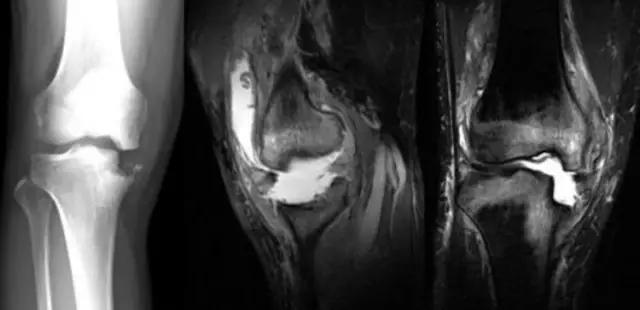

病例:游XX,男,67岁,右膝肿胀活动困难伴进行性畸形6年。疼痛不重!下图为2010年照片,DR和MR显示胫骨内侧平台骨缺损,无其他病变,很难确诊。

利用疾病发展——

下图为2014年DR,显示关节破坏严重,但疼痛不重,符合神经性关节炎的疾病特点:关节破坏极度严重,临床症状轻微!